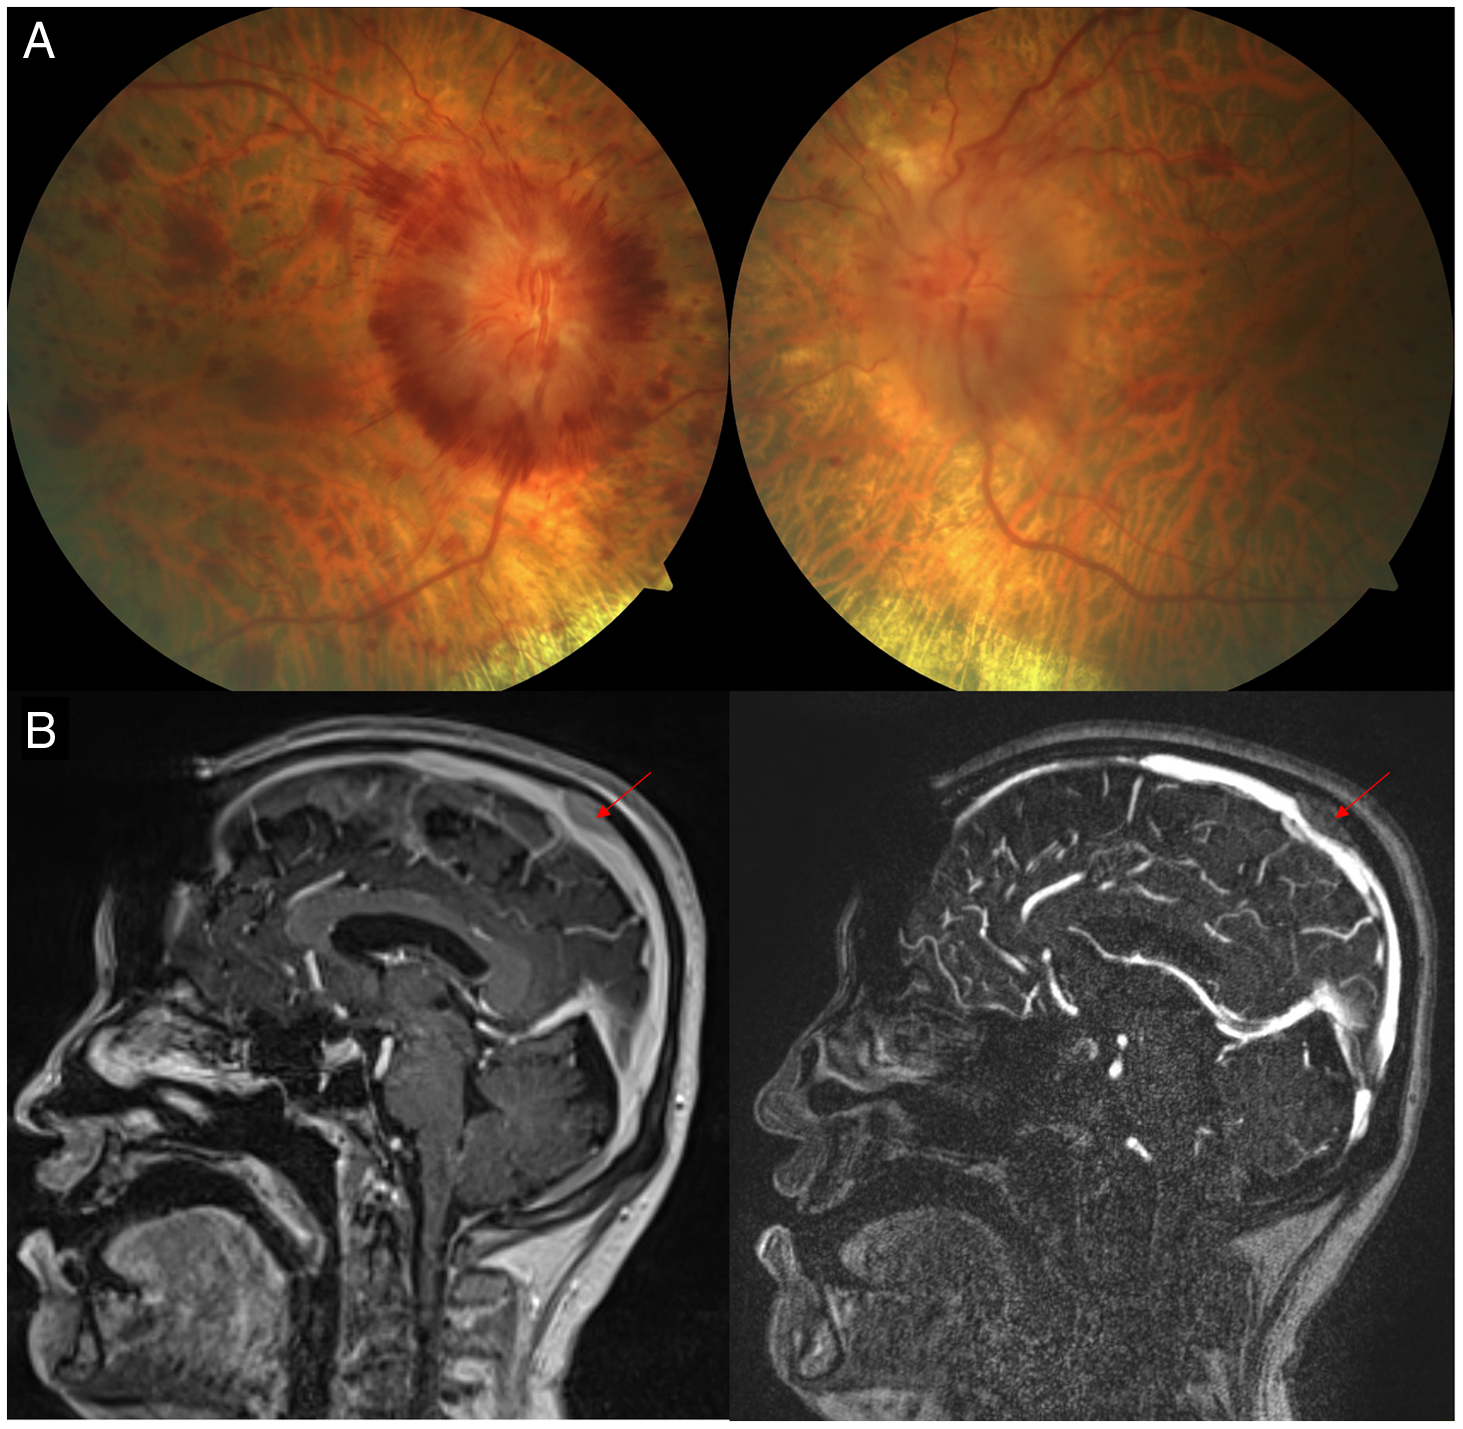

His initial examination revealed a visual acuity of 20/60 OD and 20/50 OS, full confrontation visual fields (Humphrey visual fields were not possible due to mobility issues), and no relative afferent pupillary defect. Dilated fundus examination revealed severe hemorrhagic optic disc edema in the right eye with blot hemorrhages in the macula and moderate optic disc edema in the left eye with a few blot hemorrhages OS (Figure 1). A diagnosis of papilledema related to venous hypertension due to external compression of the superior sagittal sinus by a likely metastasis was made and an MRI/MRV was performed. This revealed a calvarial lesion overlying the middle third of the superior sagittal sinus and compressing the superior sagittal sinus (Figure 2). Since he could not tolerate acetazolamide, he was switched to topiramate and a neurosurgical consultation was obtained. General anesthesia was deemed high risk due to his cardiac ventricular metastasis and he was unable to undergo CSF diversion. He was treated with radiation therapy for the calvarial metastasis.

Figure 1: (A) Fundus photographs demonstrating severe bilateral optic disc edema. (B) Sagittal magnetic resonance imaging of the brain with contrast (A) and magnetic resonance venography (B) demonstrating extrinsic compression of the superior sagittal sinus by a presumed metastasis (red arrow).